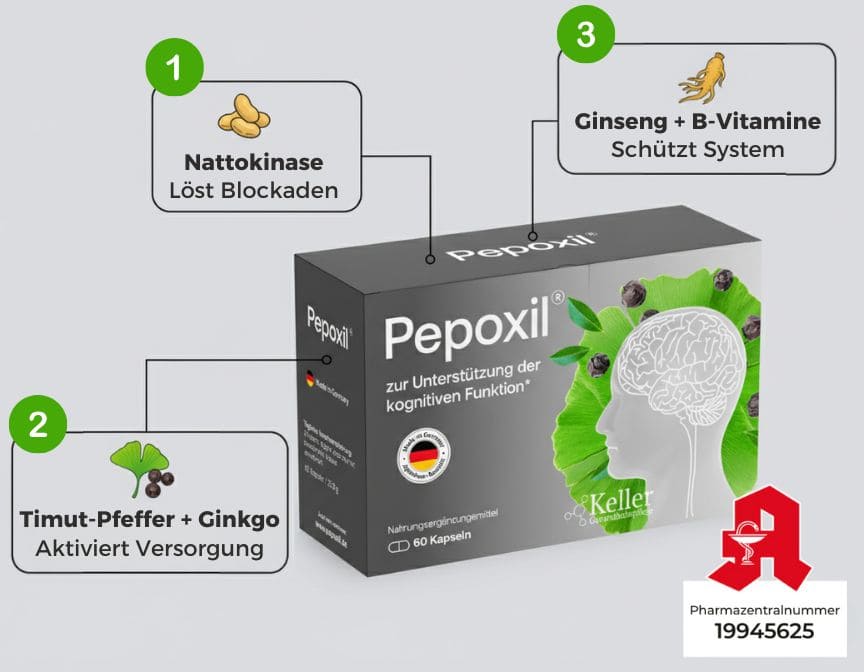

Die patentierte Formel in einer Kapsel

Die einzige Kombination in Deutschland mit Nattokinase in Pharmaqualität, Ginkgo (NACH Blockadenlösung), Timut-Pfeffer (Nepals Geheimnis) sowie Ginseng + B-Komplex (Langzeitschutz)

- Nattokinase (Pharmaqualität)

- Ginkgo (Pharmaqualität)

- Timut-Pfeffer (Pharmaqualität)

- Ginseng (Pharmaqualität)

Auf der folgenden Seite finden Sie Pepoxil mit allen Inhaltsstoffen in pharmazeutischer Qualität.

- Nattokinase

- Timut-Pfefferextrakt und Ginkgo

- Ginseng + B-Vitamine

entspricht exakt der hier beschriebenen Formel.